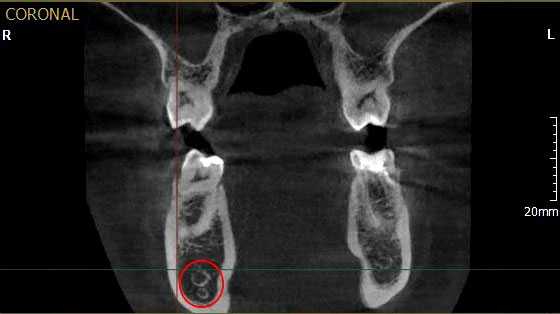

Рис. 1. Асимметричное строение нижнеальвеолярного нерва, добавочный канал в области нижней челюсти справа во фронтальной проекции конусно-лучевой компьютерной томографии от Vatech.

Лучевое обследование проводилось на различных этапах имплантации. Как правило, всем пациентам выполнялась ортопантомография на дооперационном этапе. В сложных клинических ситуациях использовались дентальная объемная томография. Изучение литературных источников по топографической анатомии лицевого скелета показало отсутствие какой-либо информации о связи строения и расположения нижнечелюстного канала с вероятностью повреждения нерва при установке имплантатов. Результаты проведенных собственных рентгеноанатомических исследований челюстно-лицевой системы позволили выделить клинически значимые особенности строения и расположения нижнечелюстного канала и нерва в теле челюсти. В этой связи к предрасполагающим анатомическим факторам риска развития хирургических осложнений при дентальной имплантации могут быть отнесены: